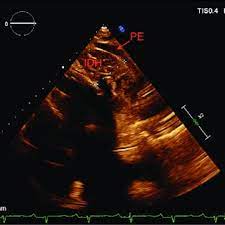

3. 신경영상검사(Neuroimaging): 뇌의 혈관 상태를 평가하기 위해 다양한 신경영상 검사가 사용됩니다. 주로 사용되는 검사에는 다음이 포함됩니다:

4. 양방향경험전도측정 (Transcranial Doppler Ultrasound): 이 검사는 뇌 혈류 속도와 흐름을 측정하는 데 사용됩니다.